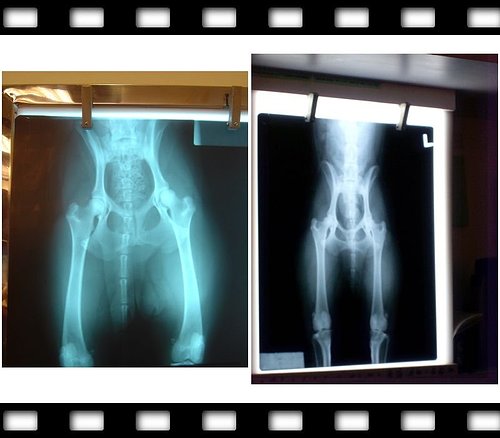

左圖的就是妮卡六個月結紮的時候,脊椎不正、雙腳沒拉直~~失敗

右圖是今天照的,山海媽說左腳包覆超過2/3 健康寶寶一枚、右腳也超過1/2很不錯

(左腳角度107、右腳106皆正常)

醫生也說妮卡骨骼很棒也很健壯,骨架也很大,所以22.5KG算正常